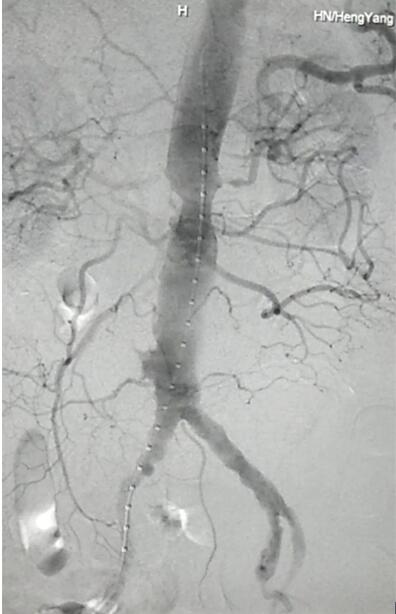

CTA檢查提示患者有腎下腹主動脈瘤。

患者因腹部搏動性腫塊行成已有4年,伴右下腹疼痛6小時入院,既往有高血壓病史,患者入院后血壓177/96mmHg,醫(yī)護(hù)人員隨即予以控制血壓、止痛處理,CTA檢查提示患者有腎下腹主動脈瘤,合并心 、肝 、肺 、腎等重要臟器疾患,根據(jù) Laplace定律,動脈瘤直徑越大壓力越大,老人動脈脆弱,動脈瘤隨時有破裂的可能性,其危險性大。血管介入科排除各種困難,在麻醉科協(xié)作下行腹主動脈瘤覆膜支架隔絕術(shù)(“褲衩”支架植入),手術(shù)持續(xù)了1個半小時,患者術(shù)后安返病房,麻醉醒后露出了微笑,向醫(yī)務(wù)人員伸出大拇指。